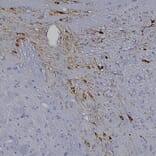

Immunohistochemistry analysis of a NBF fixed paraffin embedded human midbrain section with Anti-Tyrosine Hydroxylase Antibody (A333280) at a dilution of 1:2,000. Anti-Tyrosine Hydroxylase Antibody (A333280) labels axons transversing the striatum. Note: this antibody performs well in testing with 4% PFA and standard NBF fixed mouse, rat and human tissue.